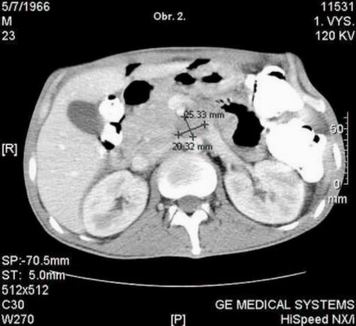

Pacient absolvuje CT vyšetření, kde je popsána velmi suspektní metastáza vpravo subpleurálně, na rozhraní S 9/10 - obr. 1., dále v retroperitoneu paket patologických uzlin 27 x 23mm - mezi aortou a dorzální plochou pankreatu, v úrovni dolního okraje pankreatu. obr. - 2., 3., 4. CT plic zobrazilo v mediastinu jen několik drobných uzlin nad bifurkací, velikosti do 9 mm. Nejsou vzhledu charakteristického pro patologické uzliny. V plicním parenchymu vpravo v S 10 subpleurálně metastatické ložisko velikosti 2O mm, polokulovité zesílení pleury kraniálně v S 1O vpravo - obr. 1. a suspektní drobné subpleurální ložisko velikosti cca 5 mm vpravo v S 2. Vlevo bez ložiskových změn, bez fluidothoraxu. Hodnoty tumormarkerů nepřesahují referenční meze - CEA 2.7 ug/l (referenční hodnota do 4.6), CA 19-9 < 2 kU/l (referenční hodnota do 37.0).